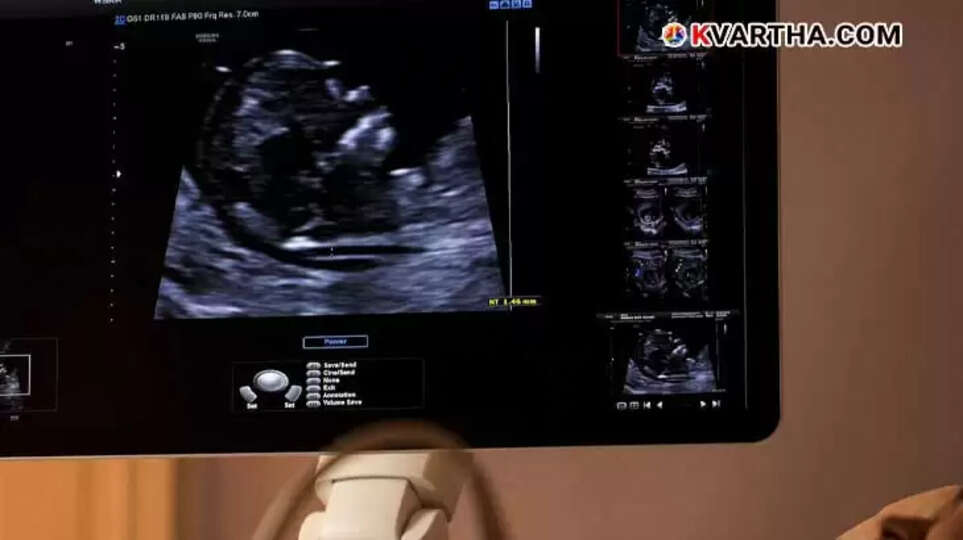

ഗർഭസ്ഥ ശിശുവിനു ഏതെങ്കിലും തരത്തിൽ കുഴപ്പങ്ങളുണ്ടോ എന്ന് നേരത്തേ തന്നെ കണ്ടെത്തുവാൻ വേണ്ടിയുള്ള സ്കാനിംഗ് മുതൽ ശരീരത്തിൽ ക്യാൻസർ ഉണ്ടോ എന്ന് തെളിയിക്കപ്പെടാനുള്ള സ്കാനിംഗ് വരെ നിലവിലുണ്ട്. ഗർഭസ്ഥ ശിശുവിൻ്റെ വളർച്ചയും, ശരീരഭാഗങ്ങൾ, ആന്തരീകാവയവങ്ങൾ, എന്നിവ സസൂക്ഷ്മമം നിരീക്ഷിക്കാനും വൈകല്യങ്ങൾ ഉണ്ടെങ്കിൽ അവ മുൻകൂട്ടി തിരിച്ചറിഞ്ഞു തക്കതായ ട്രീറ്റ്മെന്റുകൾ ചെയ്യാനും കഴിയുന്ന ഒരു സ്കാനിംഗ് രീതിയാണ് ഇവിടെ പരിചയപ്പെടുത്തുന്നത്. അതാണ് 'അനോമലി സ്കാനിംഗ്' അഥവാ TIFFA സ്കാൻ . അതിനെപ്പറ്റി വിശദമായി പറയുന്ന ഒരു കുറിപ്പ് ആണ് ഇപ്പോൾ ശ്രദ്ധയാകർഷിക്കുന്നത്.

കുറിപ്പിൽ പറയുന്നു: 'ഗർഭസ്ഥ ശിശുവിനു ഏതെങ്കിലും തരത്തിൽ കുഴപ്പങ്ങളുണ്ടോ എന്ന് നേരത്തേ തന്നെ കണ്ടെത്തുവാൻ വേണ്ടിയാണ് സ്കാനിംഗ് ചെയ്യാറ്. സ്കാനിങ്ങുകളിൽ സുപ്രധാനമായ ഒന്നാണ് അനോമലി സ്കാനിംഗ് അഥവാ TIFFA സ്കാനിംഗ്. മറ്റ് സ്കാനിങ്ങുകൾ പോലെ തന്നെ ഗർഭസ്ഥ ശിശുവിൻ്റെ വൈകല്യങ്ങൾ മനസ്സിലാക്കാൻ സഹായിക്കുന്ന ഒന്നു തന്നെയാണ് അനോമലി സ്കാനിംഗ്. ഇതിനു TIFFA (ടാർഗെറ്റഡ് ഇമേജിങ് ഫോർ ഫീറ്റസ് അനോമലീസ്) സ്കാൻ, ലെവൽ II സ്കാൻ, 20-വീക്ക് അൾട്രാസൗണ്ട് സ്കാൻ എന്നും പേരുകളുണ്ട്.

എന്നാൽ അനോമലി സ്കാനിങ്ങിനെ വ്യത്യസ്ത മാക്കുന്നത് ഇത് കുട്ടിയുടെ അവയവങ്ങളും, രൂപവും അടുത്ത് കാണാൻ സഹായിക്കുന്നു എന്നതാണ്. സാധാരണയായി ഗർഭകാല ത്തിന്റെ 18-20 ആഴ്ചകൾക്കിടയ്ക്കാണ് അനോമലി ചെയ്യാറ്, അതായത് രണ്ടാം ട്രിമെസ്റ്ററിൽ. കാരണം, ഈ കാലയളവിലാണ് കുട്ടിയുടെ ശരീരഭാഗങ്ങളും, ആന്തരീകാവയവങ്ങളും 90% വും വളർച്ചപ്രാപിച്ചിട്ടുണ്ടാവുക. ഗർഭസ്ഥ ശിശുവിൻ്റെ ശാരീരിക വികാസം, വളർച്ച , സ്ഥാനം, വൈകല്യങ്ങൾ എന്നിവ വളരെ സൂക്ഷ്മമായിത്തന്നെ അനോമലി സ്കാനിങ്ങിലൂടെ കണ്ടെത്താനാകും.

അനോമലി സ്കാൻ മറ്റ് അൾട്രാസൗണ്ട് സ്കാനിങ്ങുകൾ പോലെ തന്നെയാണ് എടുക്കുന്നത്. ഇത് തികച്ചും വേദനരഹിതമാണെന്നുമാത്രമല്ല ഗർഭിണിക്ക് റിലാക്സ് ചെയ്ത് ചെയ്യാൻ കഴിയുന്ന ഒന്നുകൂടിയാണ്. സ്കാനിംഗ് ചെയ്യുന്നത് വളരെ പരിചയസമ്പത്തുള്ള റേഡിയോളജിസ്റ്റ് ആയിരിക്കും. അൾട്രാസൗണ്ട് സ്കാനുകൾ ഭ്രൂണത്തിനോ, ഗർഭിണിക്കോ, കുട്ടികൾക്കോ, മുതിർന്നവർക്കോ ഒരുതരത്തിലുള്ള പാർശ്വഫലങ്ങളും ഉണ്ടാക്കുന്നില്ല എന്ന് പഠനങ്ങൾ തെളിയിച്ചി ട്ടുണ്ട്. അനോമലി സ്കാൻ ഒരു അൾട്രാസൗണ്ട് സ്കാൻ ആയതിനാൽ ഇത് തികച്ചും സേഫ് ആണ്.